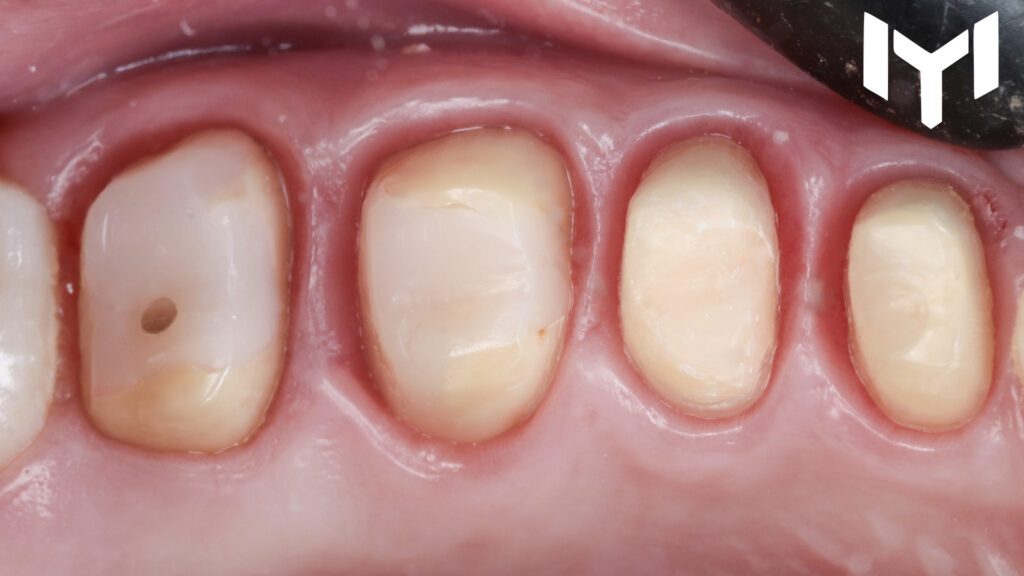

3. The Final Restoration: Zirconium after one month, the soft tissue showed remarkable health and stability. We transitioned to the final Zirconium crowns with highly finished and polished not glazed cervical collar.